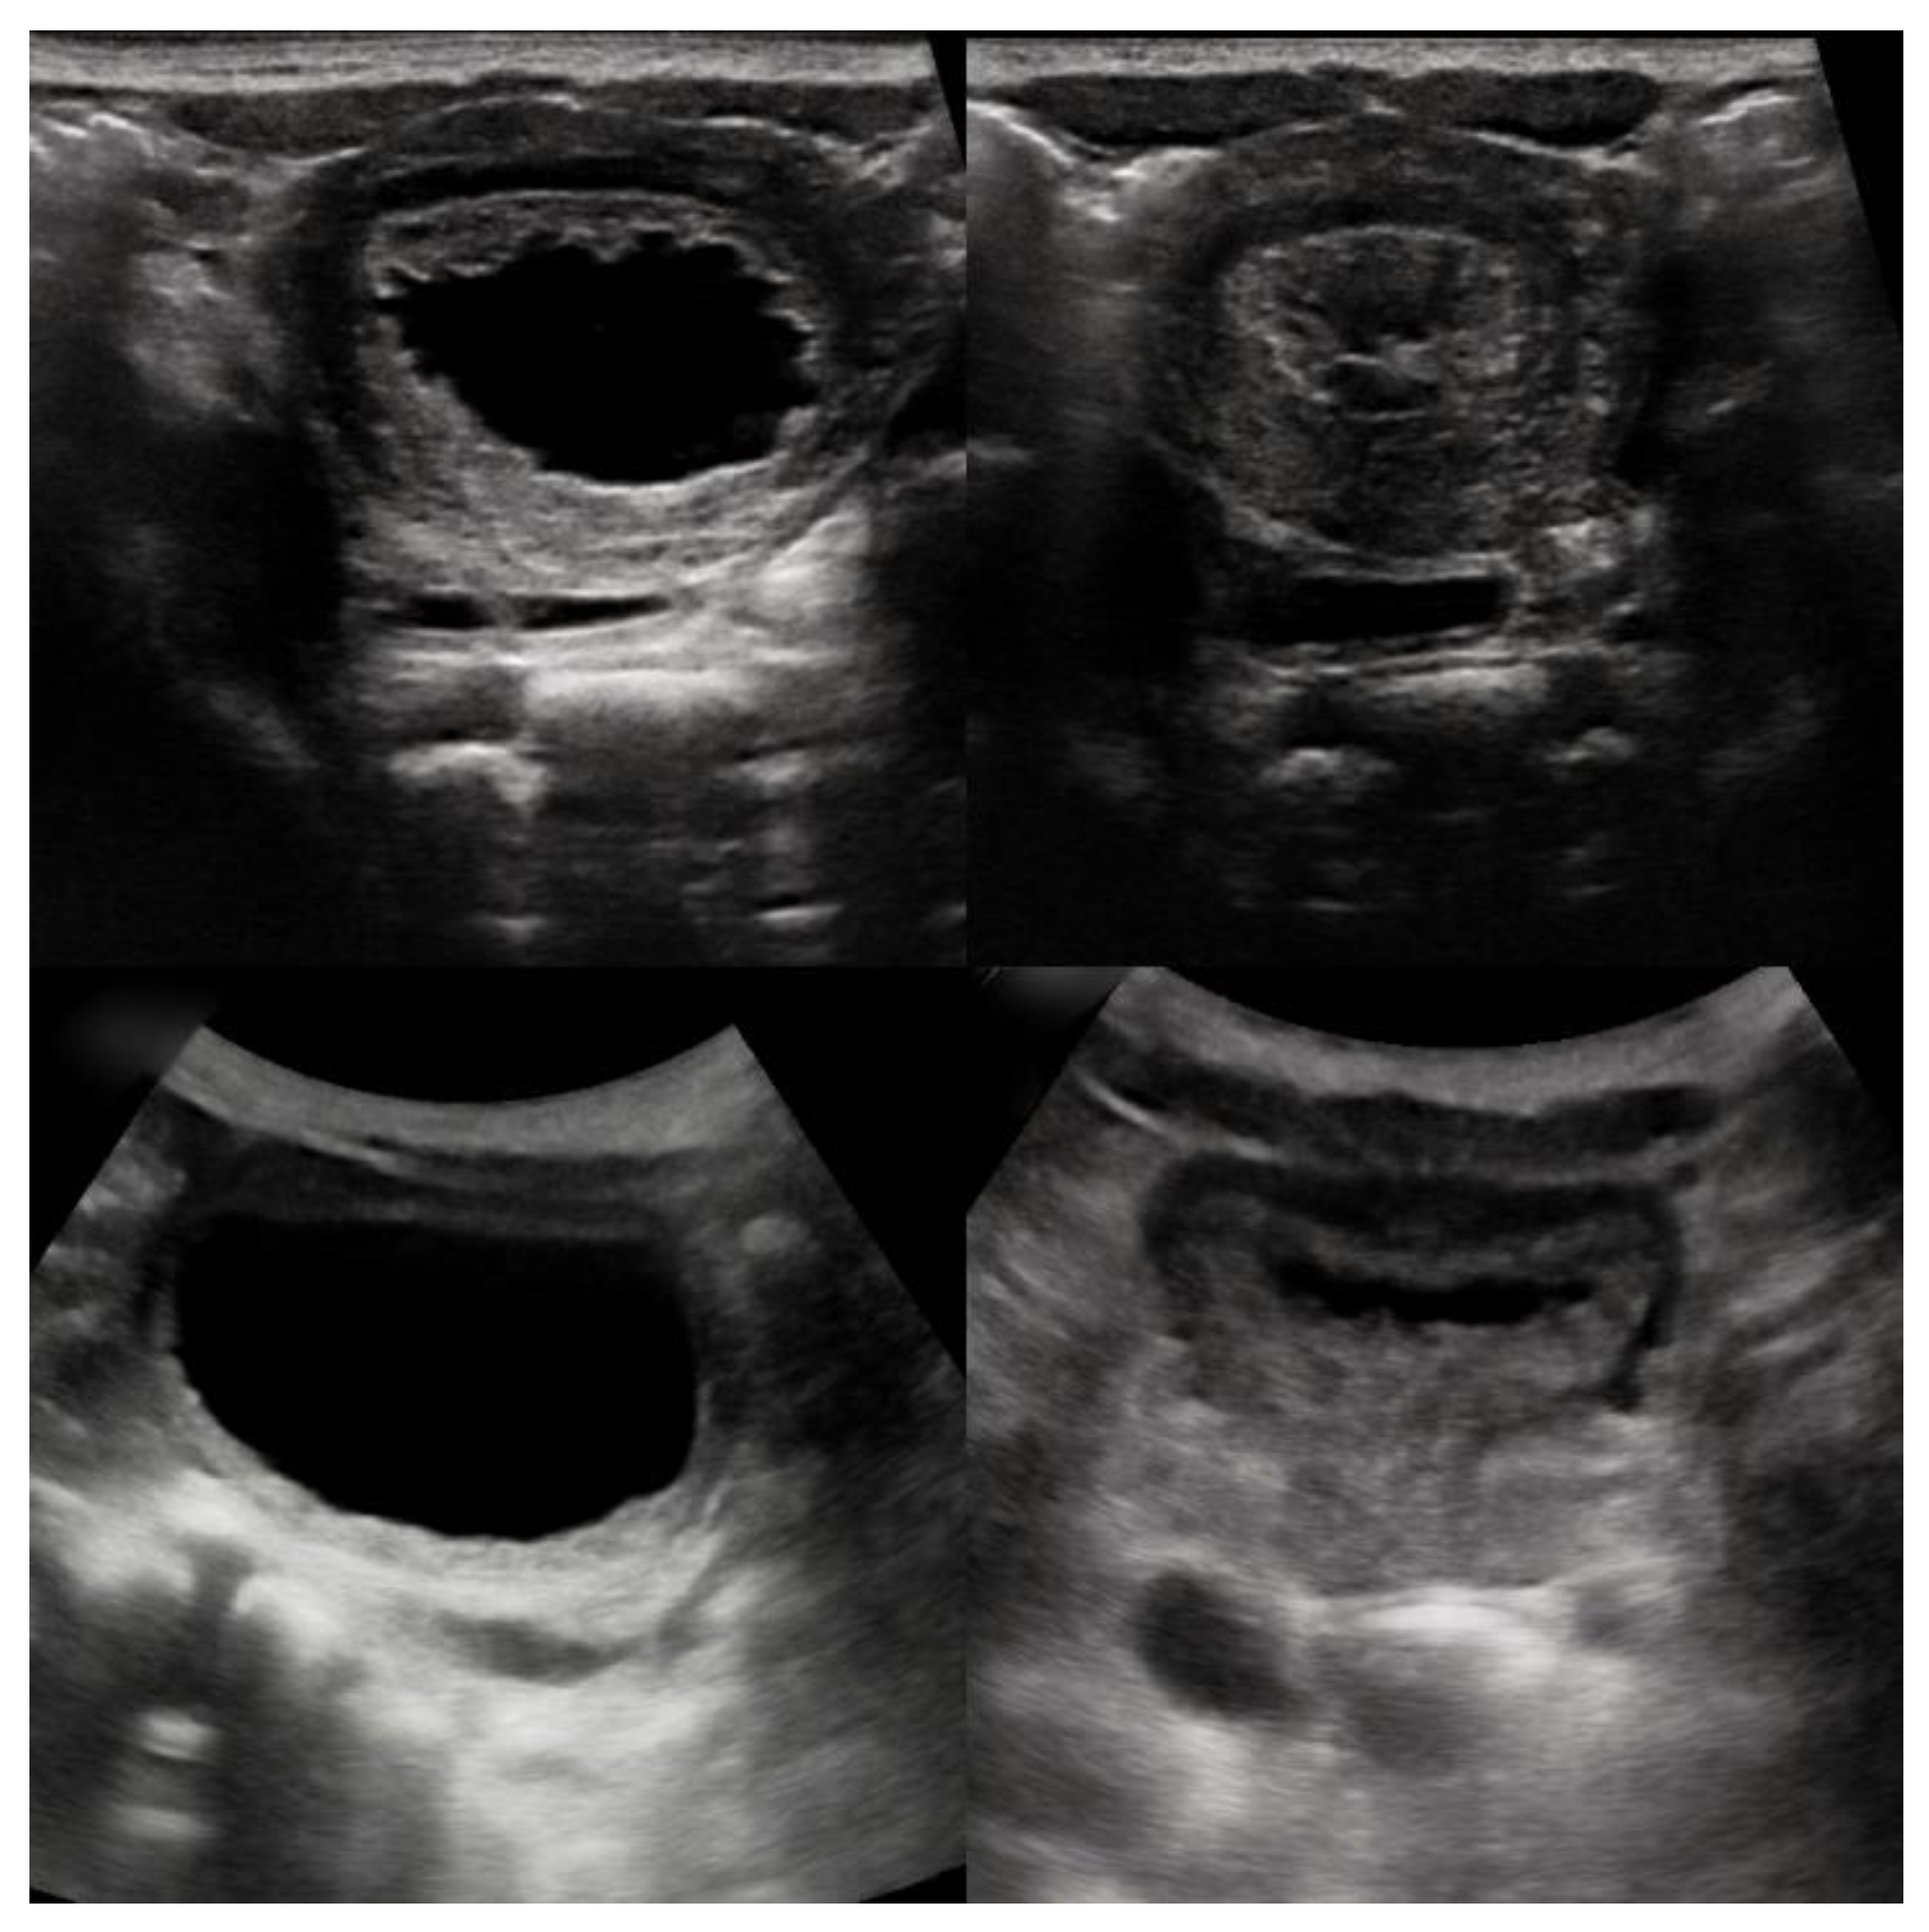

2.1. Case 1